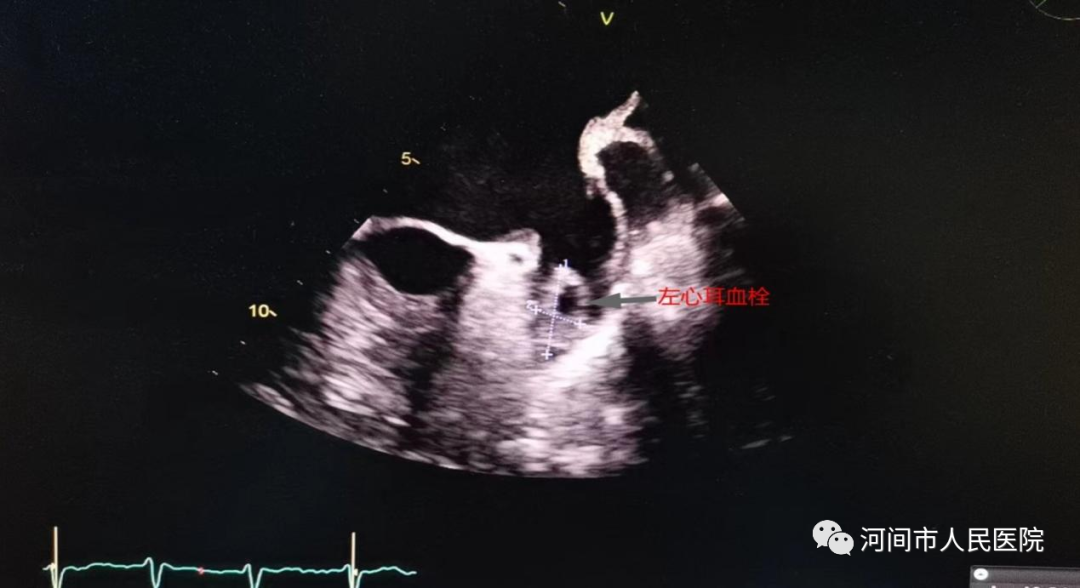

经食管超声心动图(TEE)是把超声探头放到食管内,由于探头更贴近心脏,不像经胸超声心动图那样受胸壁和肺气影响,图像显示的更清晰,特别是对左心耳等经胸超声不能看到的结构也能清晰显示。

2、怀疑左心耳和左房的血栓的患者,特别是房颤患者。